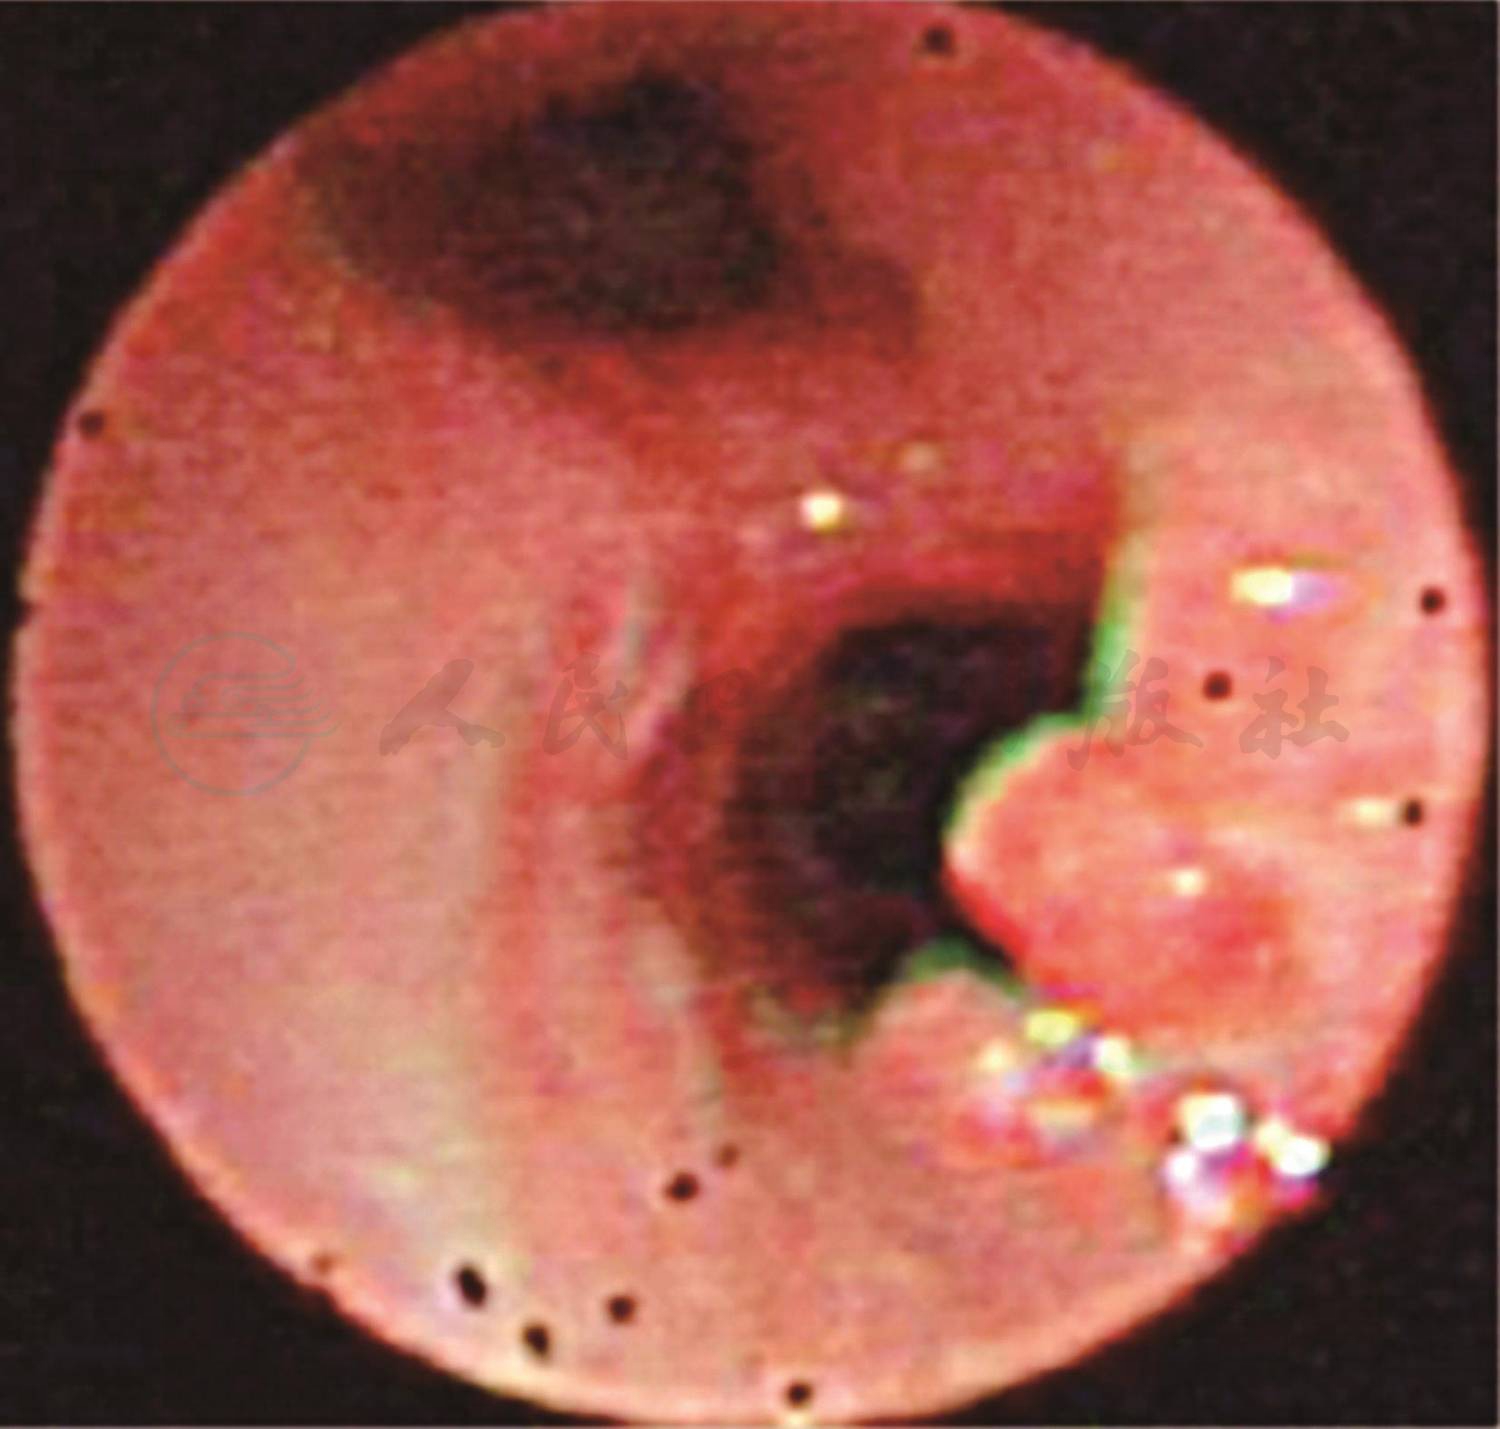

入院后予布地奈德及复方异丙托溴铵泵吸止喘,磺苄西林静脉滴注抗感染治疗。入院第2天化验结果回报:血气离子分析正常,尿、便常规正常,肝肾功能、心肌酶谱正常。CRP 1.46mg/L;结核抗体阴性;肺炎支原体抗体阳性(1:80);肺炎衣原体抗体-IgM阴性;肺炎支原体抗体-IgM阴性;肺炎支原体-DNA测定阴性(建议复查);病毒抗体八项未见明显异常。提示肺炎支原体感染不除外,予红霉素静脉滴注。免疫球蛋白:IGG 6.24g/L(正常4.81~12.21g/L),IGA 0.349g/L(正常 0.42~1.58g/L),IGM 1.38g/L(正常0.41~1.65g/L),IGA略低于正常下限。淋巴细胞亚群:总T细胞 73%(正常55%~84%),T抑制毒细胞44%(正常13%~41%),T辅助细胞23%(正常31%~60%),Th/Ts 0.52(0.71~2.78),NK细胞7%(正常7%~36%),总B细胞12%(正常5%~20%),暂不支持免疫缺陷。入院时肺CT(图1、图2):双肺野透过度明显不均匀,小气道病变,符合儿童哮喘的肺CT改变,但没有明显马赛克征改变,与闭塞性细支气管炎不相符,同时肺CT提示右肺支气管显示不佳,可能为管腔内阻塞:分泌物潴留?支气管异物?或是支气管管腔受压?因此,进一步纤维支气管镜检查成为我们关注的重点。入院第3天予完善纤维支气管镜检查:右主支气管黏膜光滑,略充血水肿,右肺下叶开口处可见黄白色异物(图3),用异物篮将异物取出,异物嵌顿处有大量肉芽组织增生(图4)。右肺上叶开口炎性狭窄明显,左肺各叶段支气管管腔开口通畅未见痰栓堵塞、狭窄及异物征象。异物取出后继续予雾化及抗感染治疗,患儿咳嗽及喘息较前明显缓解。住院治疗第6天,患儿偶有咳嗽,无喘息,肺部听诊无喘鸣音,好转出院。

图3 右肺下叶开口处异物